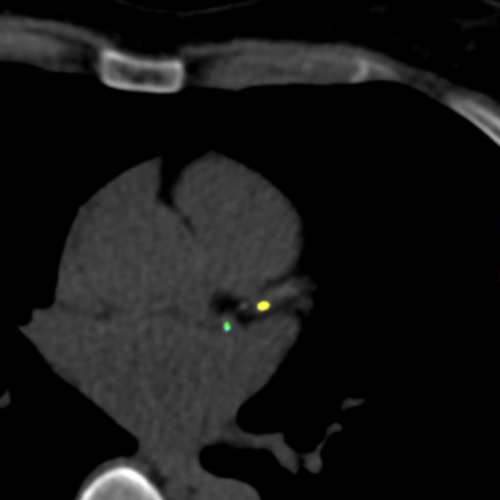

Le score calcique ( ou score Agatston) est réalisé en dépistage de la pathologie coronarienne en réalisant une quantification des calcifications sur les artères coronaires. Le calcium n’est normalement pas présent dans les artères. Sa présence est le signe de l’athérosclérose, c’est-à-dire la formation de plaques de gras qui se sont durcies avec le temps. Le score permet d’évaluer le risque cardiovasculaire (infarctus, AVC) bien avant que des symptômes n’apparaissent. Ces dépôts de cholestérol sont à l’origine de rétrécissement du calibre de ces artères et peuvent être à l’origine d’infarctus du myocarde. Cet examen est particulièrement utile chez les patients asymptomatiques présentant des facteurs de risque cardiovasculaire (hypertension, tabagisme, diabète, hypercholestérolémie), les personnes ayant des antécédents familiaux d’infarctus, d’AVC ou d’autre pathologie vasculaire, les patients sportifs asymptomatiques ou les sujets jeunes pour lequel une évaluation des coronaires est préconisés.

Le score calcique est calculé par un logiciel spécifique, qui prend en compte le volume de cette plaque, et sa densité. La somme des scores de toutes les plaques constitue le score calcique, mis au point par Agatston.

- Pour un score calcique à 0 : il n’y a pas de plaques calcifiées détectées, le risque est très faible

- Pour un score calcique 1 à 100 : il existe des dépôts légers, le risque est faible

- Pour un score calcique de 101 à 400 : il existe des dépôts modérés, le risque est modéré (risque significatif)

- Pour un score calcique supérieurs à 400 : il existe des dépôts importants, le risque est élevé